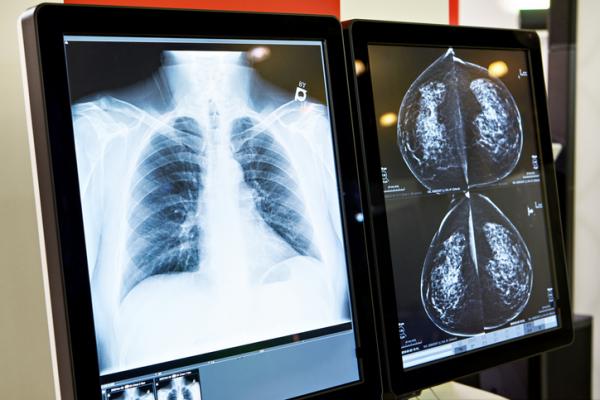

July 12, 2021 — The numbers of cancer screening tests rebounded sharply in the last quarter of 2020, following a dramatic decline in the first months of the COVID-19 pandemic, at one large hospital system in the Northeastern United States. These findings were released in a study published in Cancer Cell. The research also found an increase in racial and socioeconomic disparities among users of some screening tests during the pandemic.

Study co-senior author Toni K. Choueiri, M.D., director of the Lank Center for Genitourinary Oncology at Dana-Farber Cancer Institute, said following a dramatic decline during the first pandemic peak, there was a "substantial increase in screening procedures during the more recent periods with numbers exceeding those seen before the pandemic. However, racial disparities appear to differ between screening procedures, and are more marked in patients undergoing mammography."

During September to December 2020, cancer screening rates for breast, prostate cervical, and lung cancer recovered and exceeded numbers seen before the pandemic, the study authors said. However, the recovery was not seen in colonoscopy screening to detect colorectal cancer.

In addition to the pandemic's temporary stifling of routine cancer screening, the researchers also found an increase in racial and socioeconomic disparities with some screening tests. Significant shifts in the racial distribution of patients undergoing mammography were revealed in the decreased numbers of Non-Hispanic Black and Hispanic patients having mammographies during the period September to December 2020 compared to the three months preceding the pandemic. This contrasted with an increase in mammography tests in the whole group of patients during the last quarter of 2020, according to the study. "These findings are concerning and suggest the pandemic may accentuate racial disparities related to cancer screening," the authors noted.